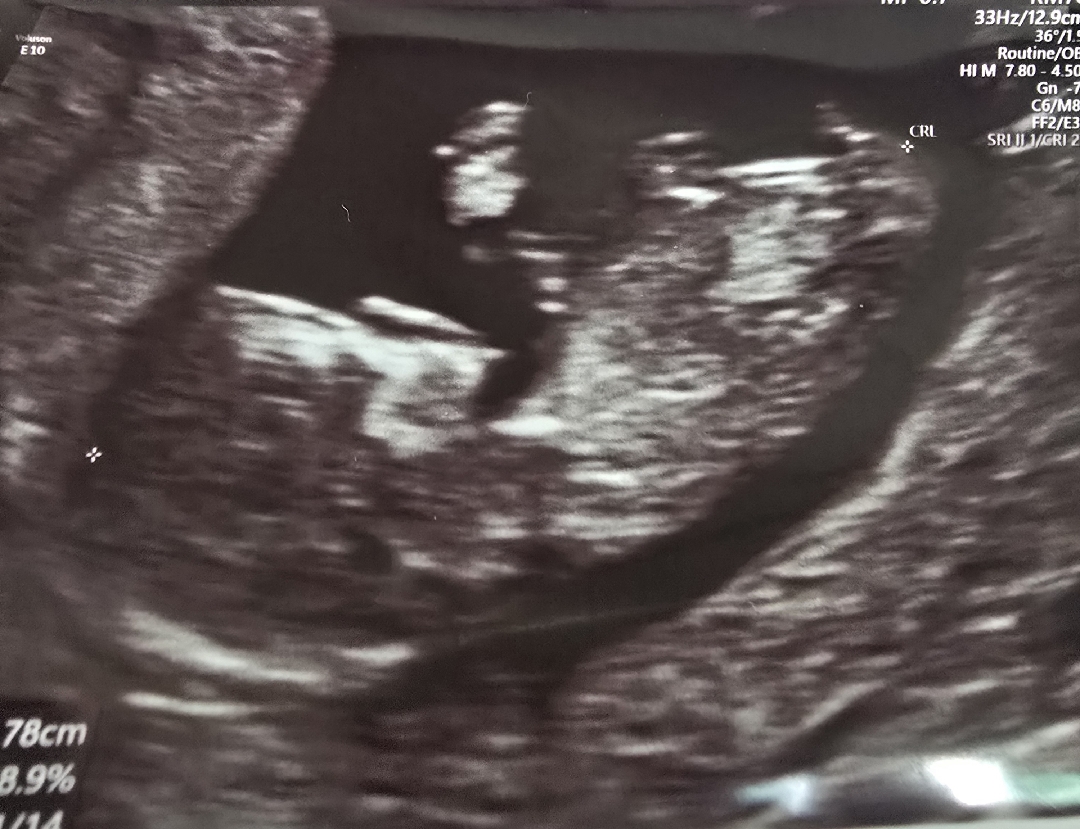

아가 성별 각도법 궁금해요ㅜㅜ

딸 셋이고 넷째를 임신한 14주 예비맘입니다 성별이 너무 궁금하네요 신랑은 딸이여도 좋다더니 아들이면 더 좋을것같다고 합니다; 혹시 이사진으로 고수님들 구별되실까요? 출산예정일이 2026-01-15이고 8월 4일에 병원갈 예정인데 4일엔 알려줄까요ㅜㅜ